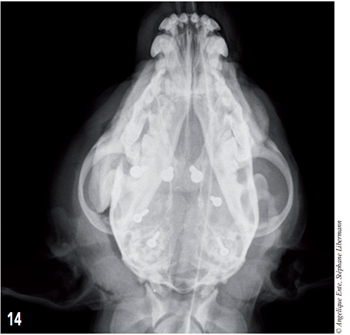

Les radiographies post-opératoires (figures 13 et 14) montrent que la couverture de l’encéphale antérieur est satisfaisante.

Figure 14 – Radiographie post-opératoire du crâne en décubitus ventral.